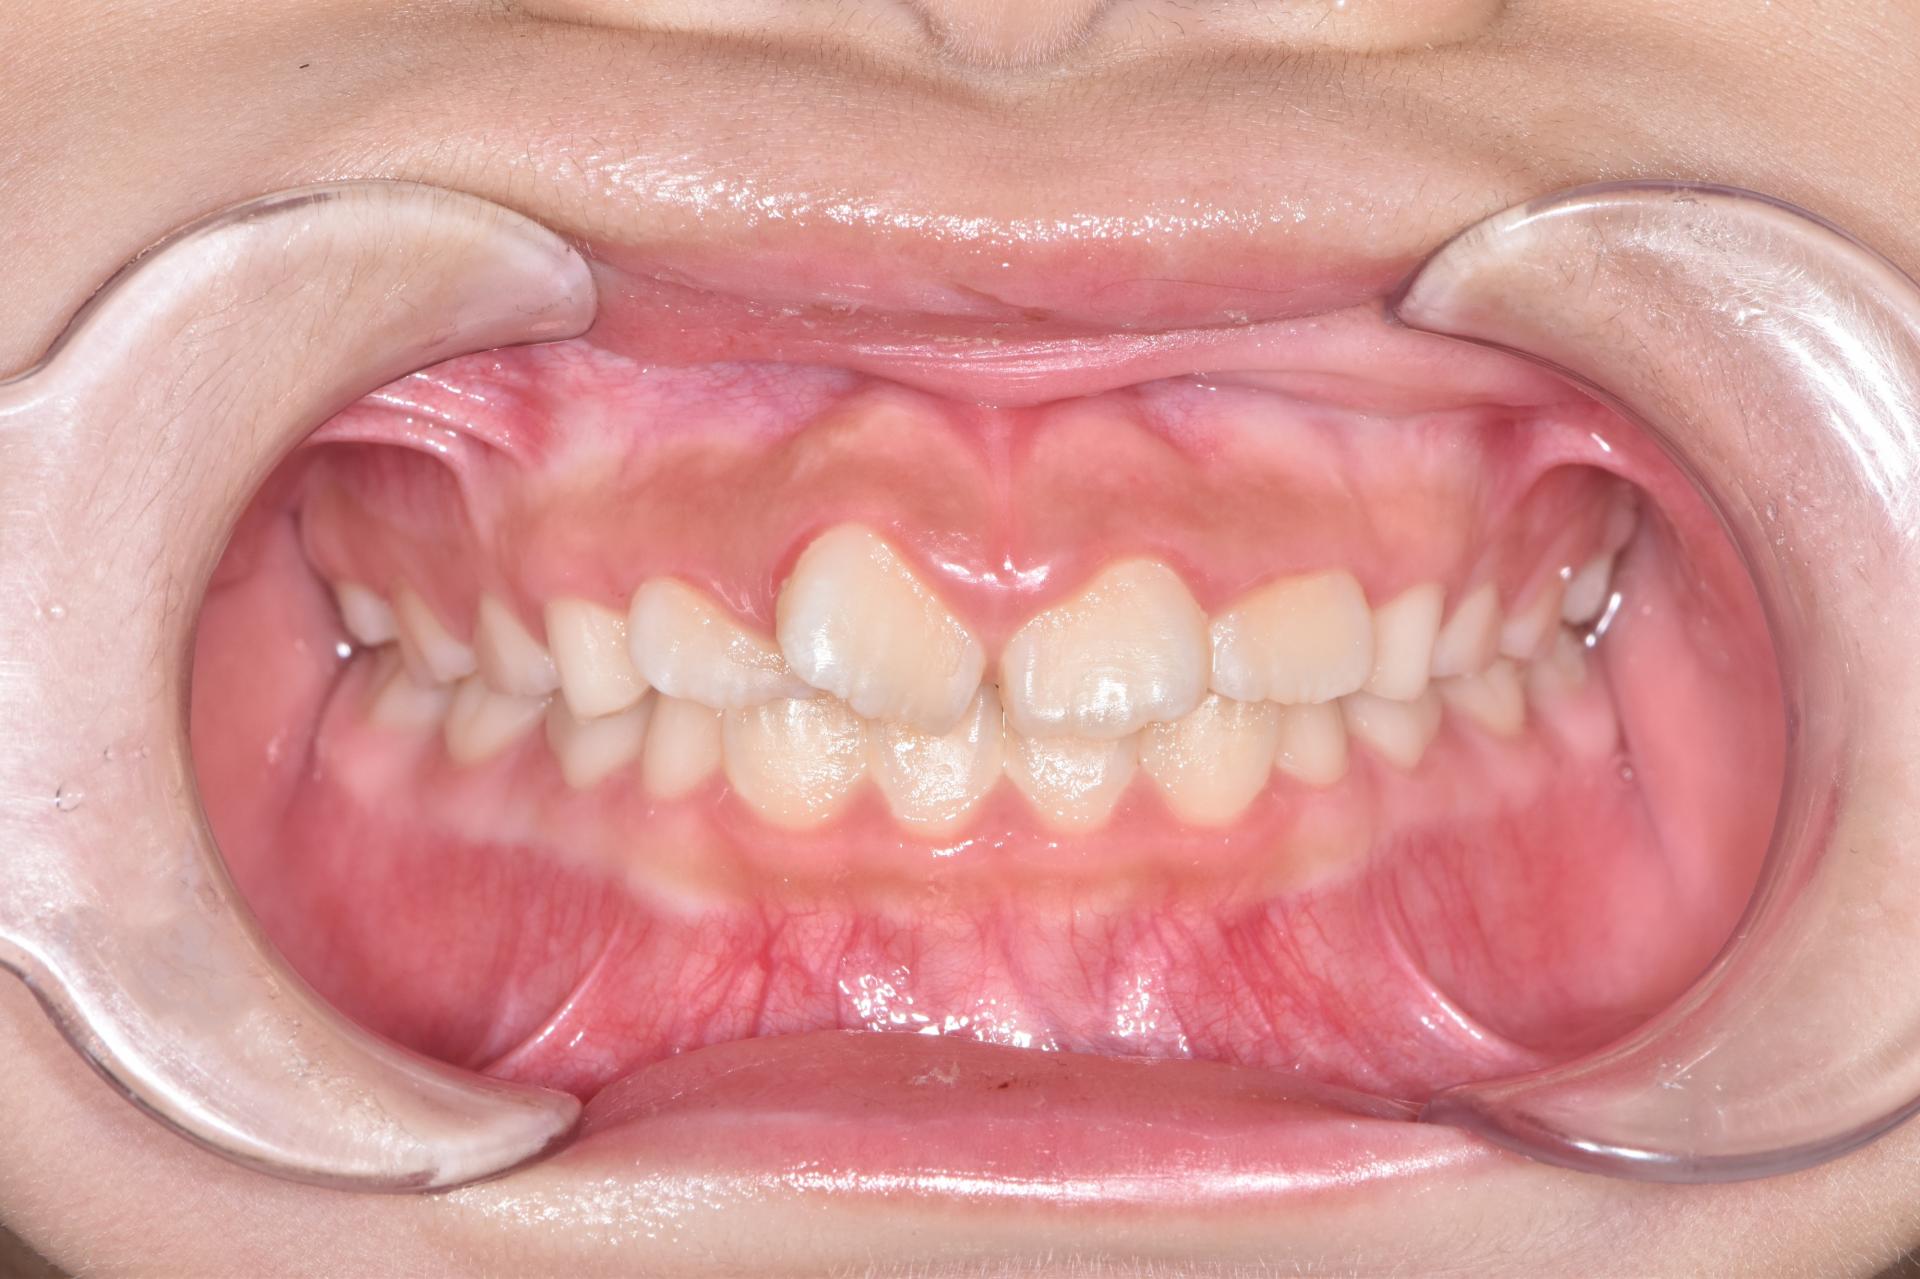

초진상태 입니다. 치아가 나올 공간이 부족하여 치아가 회전되어 삐뚤빼뚤나오고 앞니가 튀어나와있습니다.